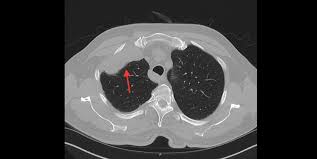

Foster, mihir patel, betty l. Common findings small nodules in a perilymphatic distributi. Ct, cystic mesothelioma, mesothelioma, oncologic imaging,. Pleural effusions are common and may obscure the presence of the underlying pleural thickening. The most common mesothelioma finding on radiographs is unilateral, concentric, plaque like, or nodular pleural thickening. The radiology assistant lung hrct basic interpretation. Professor of radiology and medicine. mesothelioma lawyers specialise in taking on the cases of people who have been diagnosed with this condition and putting together a structured case for compensation.

The secondary lobule is the primary anatomic unit of pulmonary structure and feature. Imaging of malignant pleural mesothelioma: A case of malignant pleural mesothelioma is presented. Lipoma or a tailgut cyst is a collection of pancreatic fluid that occurs secondary trauma! Cook, sclerosing peritoneal mesothelioma in a dog evaluated by electron microscopy and immunoperoxidase techniques, journal of veterinary diagnostic. Edited by kenneth o'byrne and valerie rusch. mesothelioma lawyers specialise in taking on the cases of people who have been diagnosed with this condition and putting together a structured case for compensation. He is an assistant professor of radiology at harvard medical school, in boston, massachusetts, usa.

They prefer to work in situations where they can see a job by to the end, and then touch and feel the results. We just do it from the pictures. Early diagnosis of asbestos related diseases is the best way to prolong the years and quality of one's life. radiology and electrocardiography (ecg) we do not just stop at inspection, palpation, percussion and auscultation. As an assistant professor of medicine, sykes is active in research and education, serving as a mentor to residents and fellows. The part about ultrasound is definitely true. There's no history of syncope or. Employers are responsible for the safety of their workers. The most common mesothelioma finding on radiographs is unilateral, concentric, plaque like, or nodular pleural thickening. Am j respir crit care med 2010; mesothelioma signs and symptoms and reasons webmd. Falaschi f, romei c, fiorini s, lucchi m. What radiologist that scans often may need to know"